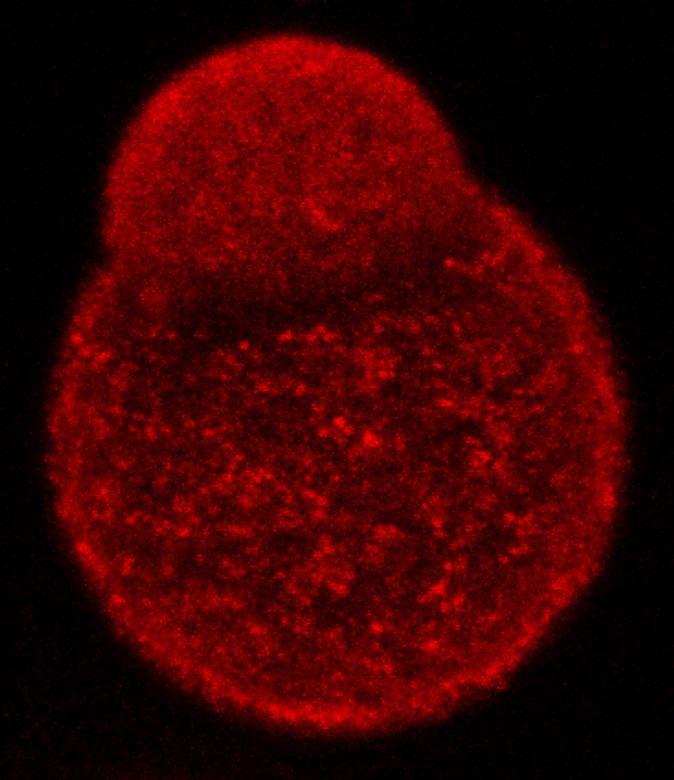

Tres grupos de investigación europeos, entre ellos uno del Instituto de Salud Carlos III (ISCIII), han conseguido reproducir, de manera simultánea e independiente, la formación de células gigantes o titanes de un hongo patógeno in vitro, sin necesidad de utilizar animales infectados.

Con respecto al hallazgo, este científico explicó que “en el caso de los hongos patógenos es importante entender como estos microorganismos son capaces de sobrevivir en nuestro interior y como evaden el sistema inmunológico. En concreto, esta levadura es capaz de multiplicar su tamaño por casi mil veces, formando unas células denominadas gigantes o titanes, las cuales son casi imposibles de eliminar por el sistema inmune”.

Pero, además de la importancia de estas células en la biología de este patógeno, los expertos en su estudio se enfrentaron durante años al hecho de que este fenómeno no era fácil de reproducir en condiciones de laboratorio y la única manera de estudiarlas, era aislarlas de animales infectados, lo que conllevaba limitaciones económicas y bioéticas.

Además, los científicos descubrieron que el suero de mamífero es un inductor muy potente del fenómeno del “gigantismo”, así como el dióxido de carbono, un gas que se encuentra en concentraciones muy significativas en el pulmón. Además, usando las nuevas tecnologías de secuenciación masiva, han identificado nuevos genes que regulan este proceso.